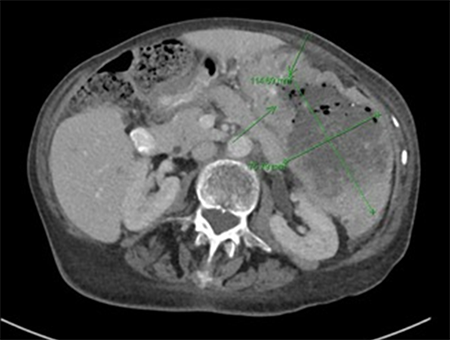

A CT of the abdomen and pelvis with oral and intravenous contrast demonstrated interval enlargement of the splenic mass from 9.7x6.7cm six months prior to 11.5x7.6 cm, with heterogeneous areas of air-containing parenchyma indicating necrosis (Figure 2).

Figure 2. Large 11.5x7.6cm splenic mass with heterogeneous areas of air-containing parenchyma indicating necrosis

The anterior surface of the mass appeared to invade the greater curvature of the stomach, with ingested oral contrast extending through a fistulous tract between the two. Additionally, the mass directly abutted the left hemidiaphragm, the transverse colon, and the tail of the pancreas.